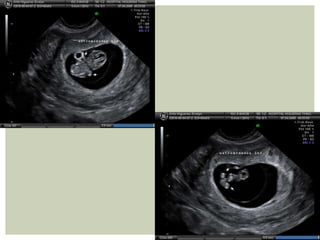

 Estructura anecoica con reborde

periférico altamente ecogénico

que corresponde al trofoblasto

 Signo de doble saco decidual permite diferenciación

de colección endometrial o seudosaco

 DSM es promedio de 3 diámetros del saco

 Crece 1 mm por día

Primera estructura visible:

4º sem TV

5º sem abdominal

bHCG>1000